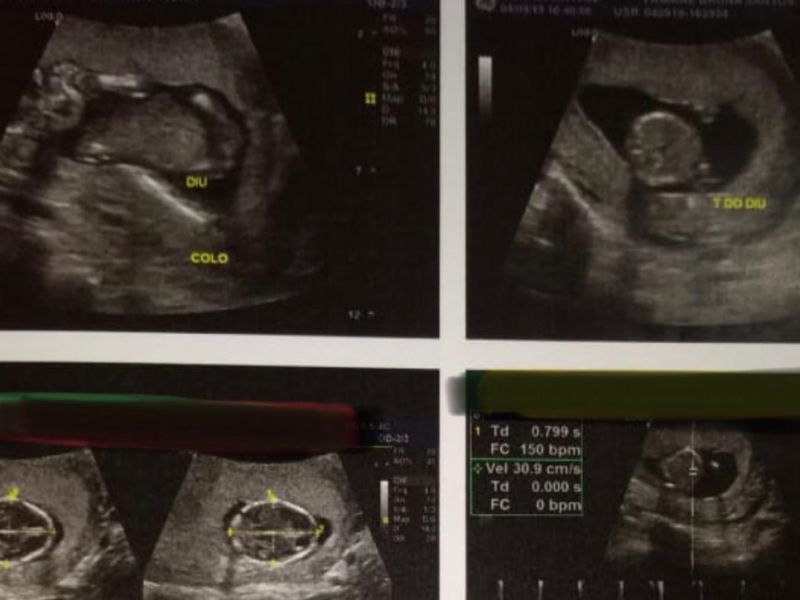

11 de setembro de 2019 Conselho de Medicina vai investigar aborto de paciente que recebeu DIU de enfermeiro em Penedo